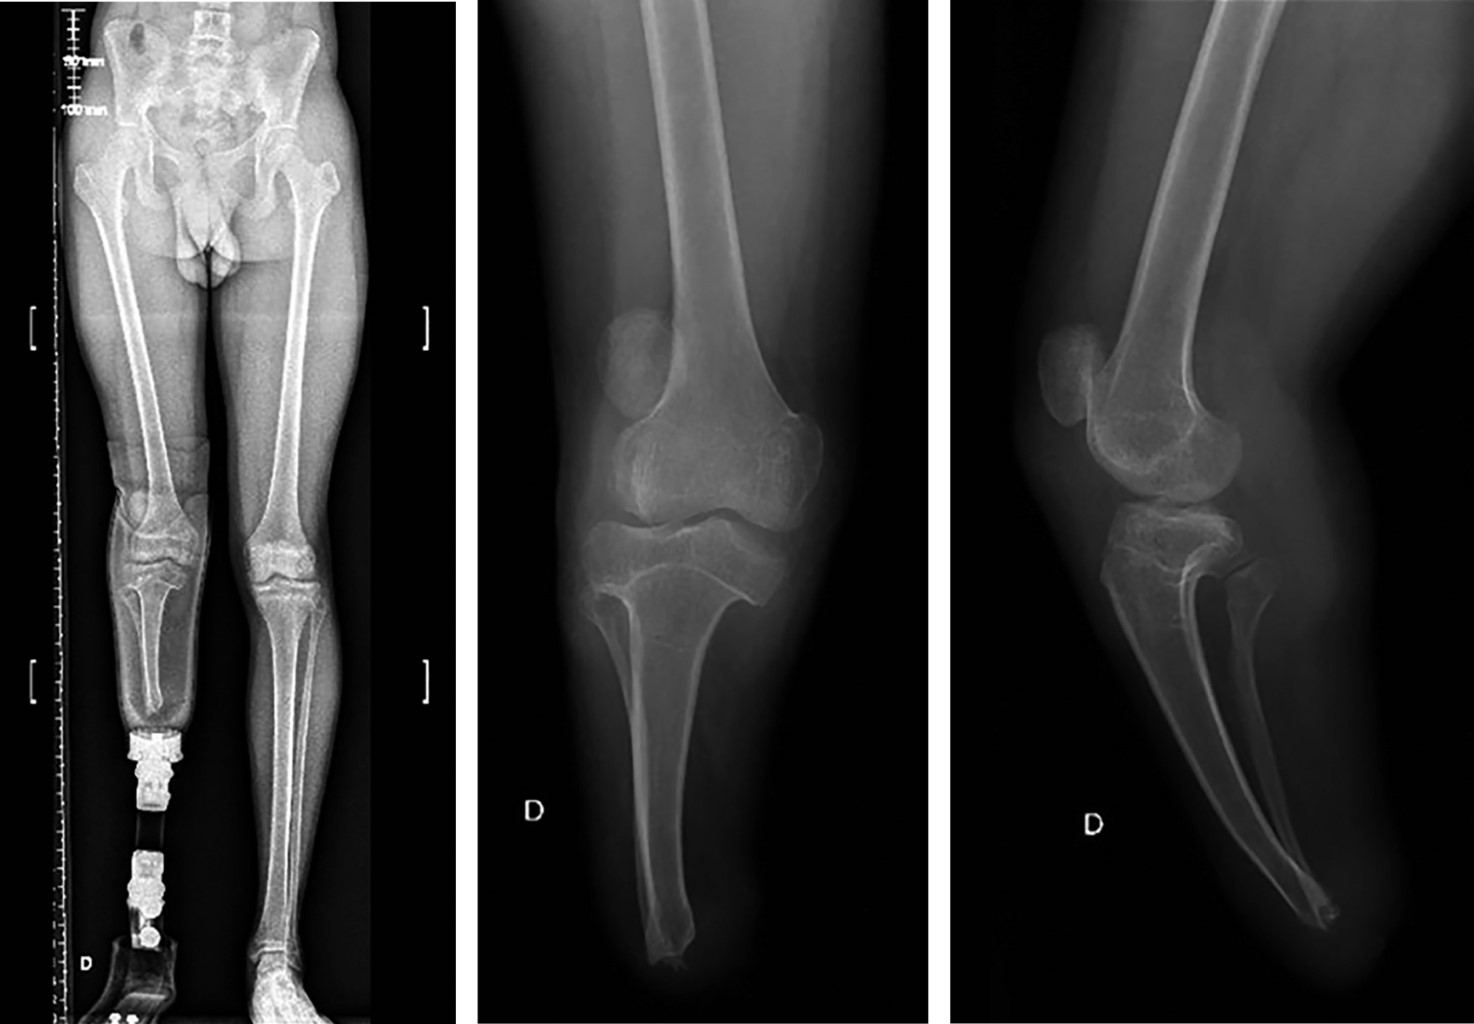

La inestabilidad patelofemoral es una condición multifactorial que abarca un espectro de manifestaciones que van desde subluxaciones hasta luxaciones completas de la rótula. Desde el punto de vista etiológico, puede originarse a partir de diversas anomalías anatómicas, incluyendo la alineación de las extremidades, la morfología ósea de la articulación patelofemoral y la integridad de los estabilizadores estáticos y dinámicos. Los pacientes con amputación por debajo de la rodilla tienen un mayor riesgo de experimentar inestabilidad patelofemoral. Este informe describe un caso que involucra a un paciente con inestabilidad patelofemoral y una amputación transtibial, tratado de manera efectiva con realineación distal y estabilización patelar lograda mediante la reconstrucción del complejo patelofemoral medial (CPFM).

Figura 1